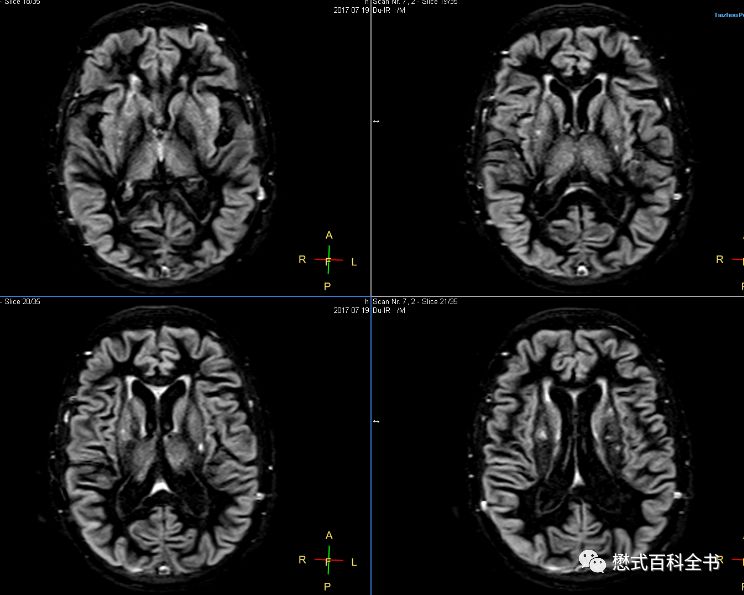

采用连续两个反转脉冲作为准备部分的反转恢复序列又叫做双反转序列(Dual IR)。在双反转序列中就存在两个反转时间(TI1和TI2),通过合理的设置这两个时间可以选择性的抑制两种组织,比如在头颅扫描中,可以通过抑制脑脊液和脑白质信号达到脑灰质成像(Grey Matter only image)的目的,或者抑制脑脊液和脑灰质信号来实现脑白质成像(White Matter only image)。

前面也介绍了脑灰白质成像的专用序列,其实就是采用双反转序列,通过两次反转选择性的抑制两种组织,从而达到只进行某一种组织的成像效果。

在飞利浦中,原始序列里有专门的脑灰质成像(Grey Matter only)序列和脑白质成像(White Matter only)序列。理论上,1.5T和3.0T由于组织的T1值不同,这个参数有变化,但是我发现,1.5T和3.0T基本上参数设置是一致的。脑灰质成像(Grey Matter only)序列

TR=11000ms或者10500ms,大于10000ms,因为有两个反转;TE=25ms或者20ms;

个人感觉,1.5T效果比3.0T好,可能是1.5T脑组织对比度优于3.0T的原因。